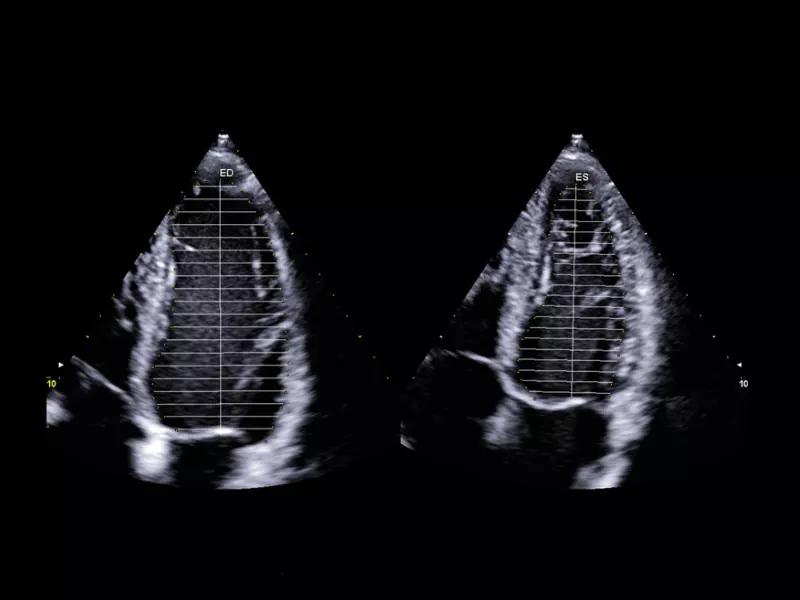

MyLab™E80 - AutoEF

MyLab™E80 - AutoEF

MyLab™X90 - AutoEF Automatic Ejection fraction assessment of the left ventricle

MyLab™X90 - AutoEF Automatic Ejection fraction assessment of the left ventricle

MyLab™X5 - AutoEF

MyLab™X5 - AutoEF

MyLab™X6 - AutoEF

MyLab™X6 - AutoEF

MyLab™X7 - AutoEF

MyLab™X7 - AutoEF

MyLab™Omega - Zero-Click AutoEF

MyLab™Omega - Zero-Click AutoEF

MyLab™A50 - AutoEF

MyLab™A50 - AutoEF

MyLab™A70 - AutoEF

MyLab™A70 - AutoEF